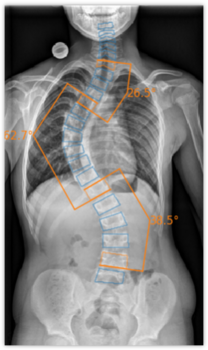

Die zugrunde liegende Technologie der Software von ImageBiopsy Lab basiert auf maschinellem Lernen – also darauf, dass Computer aus Beispielen vorheriger Fälle lernen. Tausende Röntgenbilder, von Ärzt*innen manuell markiert, dienen als Trainingsdaten: Sie zeigen der Software, wo etwa Gelenkspalten, Knochenwinkel oder Brüche liegen. Das System lernt, ähnliche Strukturen in neuen Bildern automatisch zu erkennen und zu vermessen. Die Lösungen von ImageBiopsy Lab erkennen in Sekundenschnelle relevante Strukturen, messen definierte Parameter und erzeugen einen strukturierten Analysebericht – standardisiert und reproduzierbar. So entsteht eine belastbare Grundlage für Diagnostik, Verlaufskontrolle und Therapieentscheidungen.

Heute hat ImageBiopsy Lab sieben zertifizierte Module ((MDR/TÜV SÜD, teil auch von der US-FDA) auf dem Markt. Sie decken zentrale anatomische Regionen wie Knie, Hüfte, Wirbelsäule oder Fuß ab und liefern standardisierte Analyseberichte, die in radiologischen und orthopädischen Praxen in Deutschland, Österreich und der Schweiz eingesetzt werden. Installiert „on-premise“ laufen sie im Hintergrund und liefern Zusatzinformationen direkt zum Bild.